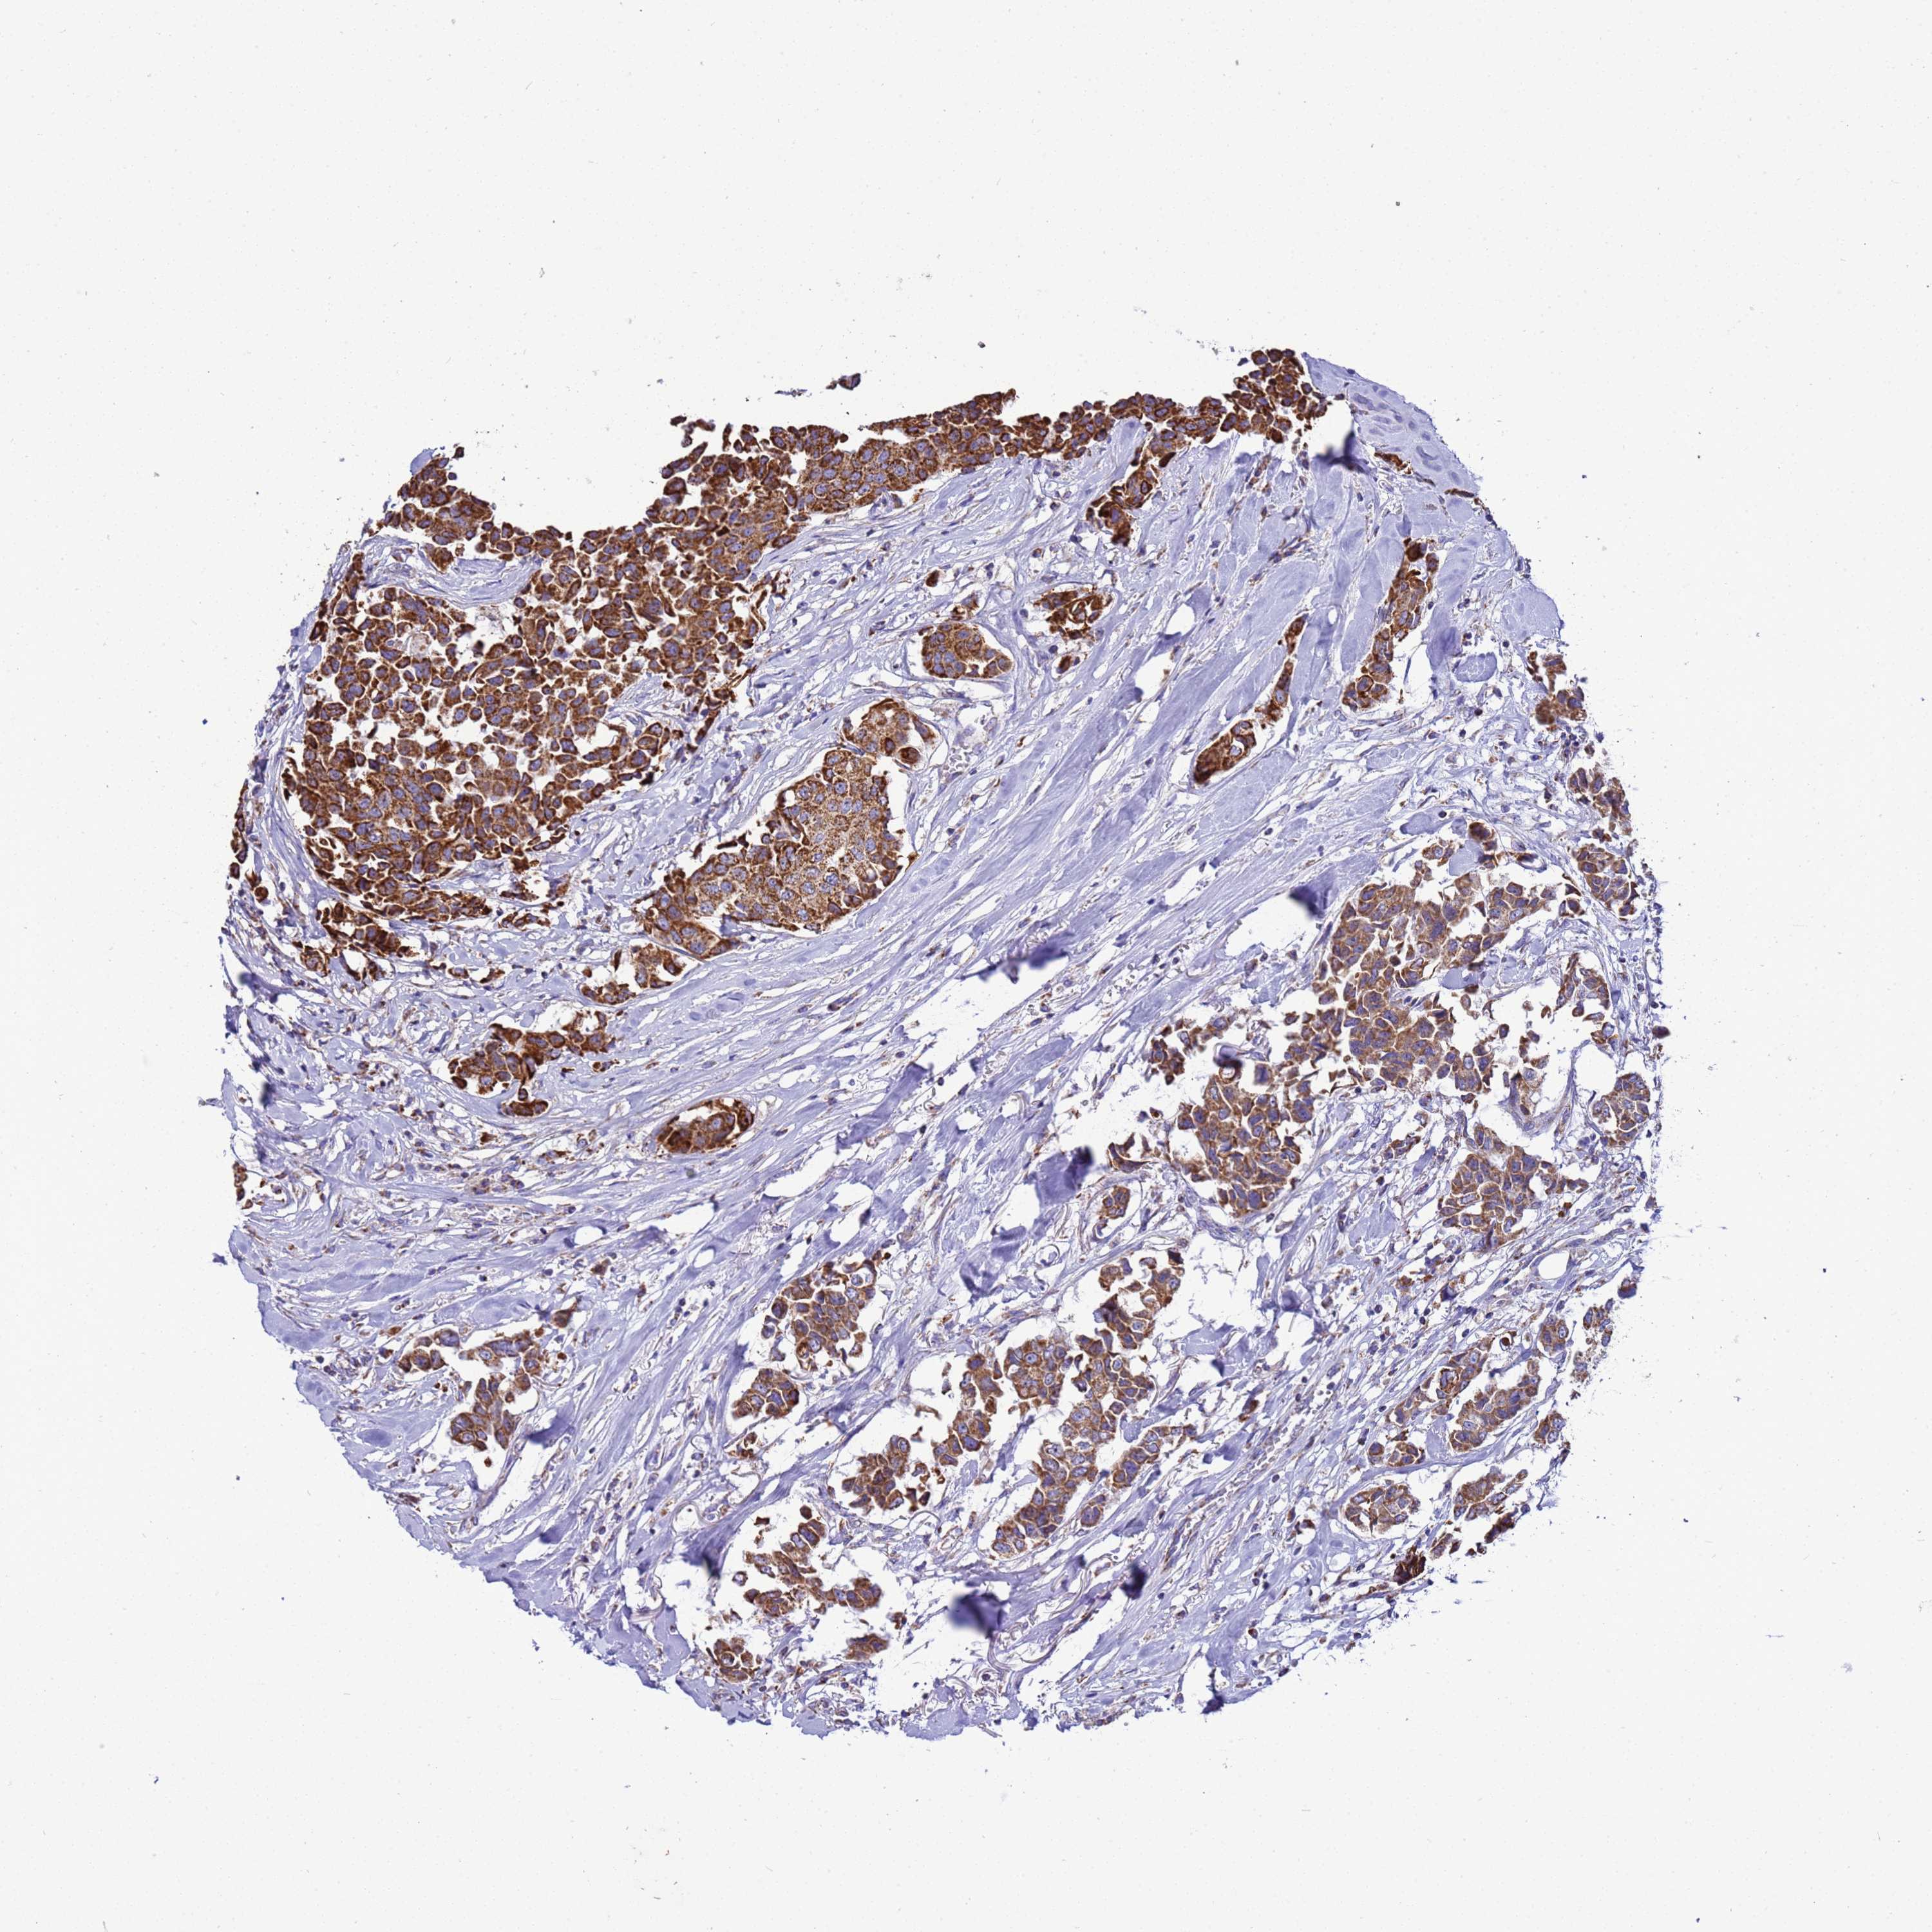

CANCER BREAST CANCER Show tissue menu

BRCA TCGA BRCA VALIDATION PROTEIN EXPRESSION